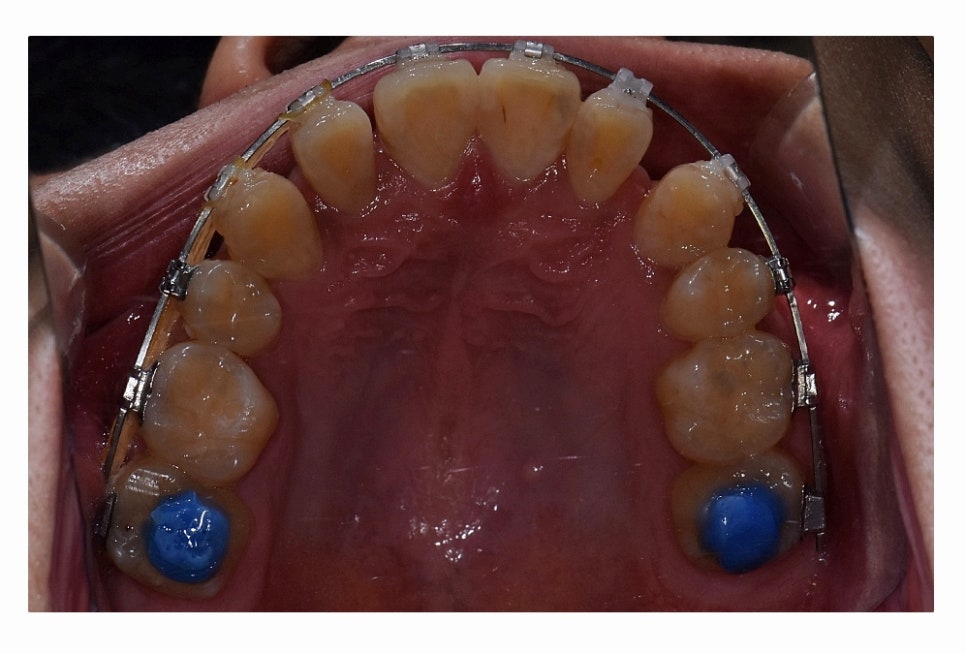

오늘 보시는 환자분의 사례처럼 덧니가 치아끼리 겹쳐 있는 경우에

치아의 이동 공간 확보를 위해서 덧니 발치 필요한 사례였으며

교합과 치아교정 후 얼굴 변화를 고려할 때도 치아교정 과정에서

발치가 필요한 사례였다고 볼 수 있어요.

일반적으로는 송곳니 옆의 작은 어금니를 발치하는

경우가 대부분이며 손상이 심한 치아가 있는 경우에는

손상도가 심한 치아를 발치하는 경우도 있어요